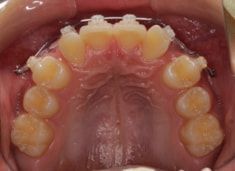

治療前

治療開始時